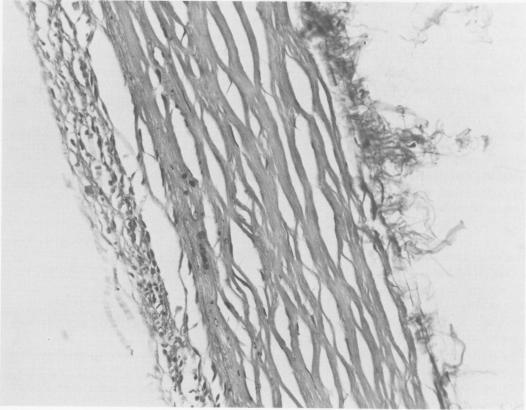

We have used two methods to maintain ductal ppatency in 13 newborns during surgery for congenital cardiac malformations: prostaglandin E1 (PGE1) infusion for the short-term and formaldehyde infiltration of the ductus arteriosuos (FID) for the longer term. PGE1 increased the arterial oxygen saturation, leading to stable intraoperative hemodynamics in the six infants in whom it was used. FID was used in all 13 patients. Four of these patients died in the hospital, all with the ductus open. Of the nine early survivors, all required an additional shunt procedure. The five long-term survivors had the second palliative operation immediately, three hours, three days, two and one-half months, and four and one-half months after FID. We continue to use PGE1 to maintain ductal atency through operation, but use aortopulmonary anastomosis in the newborn period rather than FID.

我们采用了两种方法在13例先天性心脏畸形手术的新生儿中维持动脉导管通畅:短期使用前列腺素E1(PGE1)输注,长期使用动脉导管甲醛浸润(FID)。PGE1提高了动脉血氧饱和度,使使用该药物的6例婴儿术中血流动力学稳定。13例患者均使用了FID。其中4例患者在医院死亡,均为动脉导管未闭。9例早期存活者均需要再次进行分流手术。5例长期存活者在FID后立即、3小时、3天、2个半月和4个半月进行了第二次姑息性手术。我们继续使用PGE1在手术过程中维持动脉导管通畅,但在新生儿期采用主动脉-肺动脉吻合术而非FID。